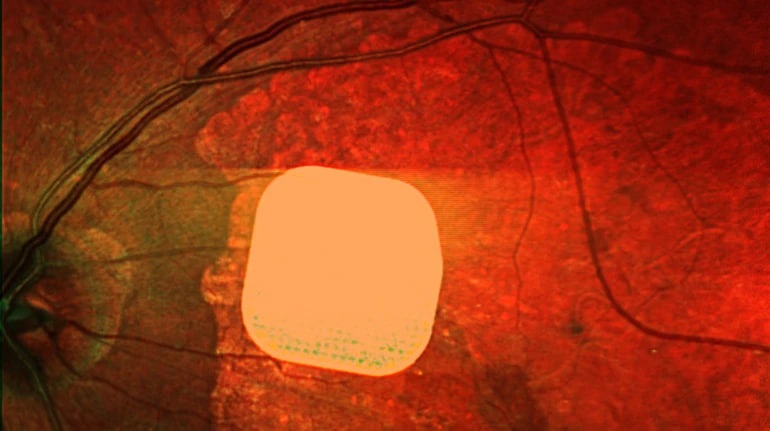

Британські лікарі з лондонської клініки Moorfields Eye Hospital спільно з колегами із інших європейських медичних закладів розробили електронний імплант Prima, який допомагає частково відновити зір у пацієнтів із макулодистрофією – однією з основних причин втрати зору після 50 років. Цей мікрочип розміром лише 2×2 міліметри встановлюють під сітківку ока, а пацієнт користується спеціальною системою окулярів доповненої реальності для отримання зображення. У дослідженні взяли участь 38 пацієнтів, які після імплантації змогли розрізняти літери, цифри та слова. Лікарі вважають, що ця технологія відкриває нові можливості для людей з важкими зоровими порушеннями, допомагаючи покращити їхню якість життя та незалежність.